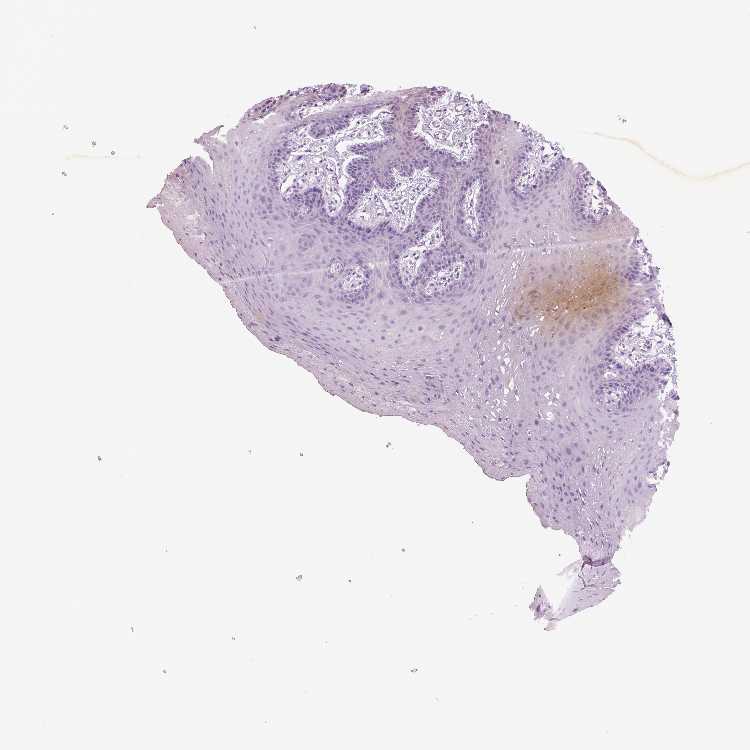

TISSUE PRIMARY DATA ORAL MUCOSA Show tissue menu

ORAL MUCOSA - Antibody stainingi

Antibody staining in the annotated cell types in the current human tissue is reported as not detected, low, medium, or high, based on conventional immunohistochemistry profiling in selected tissues. This score is based on the combination of the staining intensity and fraction of stained cells.

Each image is clickable and will lead to virtual microscopy that enables deeper exploration of all samples and also displays staining intensity scores, fraction scores and subcellular localization as well as patient and tissue information for each sample.

Squamous epithelial cells Not detectedNot detectedNot detectedNot detectedNot detectedNot detectedNot detected